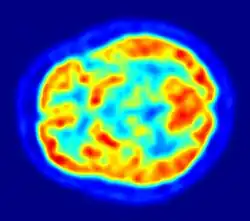

Paedophiles show pathological personality traits such as anxiousness, inhibited personality, lack of assertiveness and impaired neuro-cognitive functioning (Black, 2000; Cohen et al., 2002). Dennison, Stough, and Birgden (2001) found paedophiles had significantly higher neuroticism and significantly lower extraversion and conscientiousness when compared to non paedophiles. Paedophiles assessed with neuropsychological batteries (e.g., the Halstead-Reitan and Luria-Nebraska Batteries) show greater impairments largely in verbal and visual-spatial abilities than other nonsexual offenders, or those who commit sexual crimes against adults (Langevin, Wortzman, Wright, & Handy, 1989).

When paedophiles are compared with non criminal community control groups or with men convicted of non sexual crimes, convicted paedophiles typically score lower in intelligence and also have lower immediate and delayed memory performance (Blanchard et al., 2007). Cognitive deficits in paedophiles can be seen to be mediated by the prefrontal cortex, which may account for their behavioural disinhibition, disinhibition of automatic motor responses, working memory deficits, and impairment of cognitive flexibility (Joyal, Black, & Dassylva, 2007).